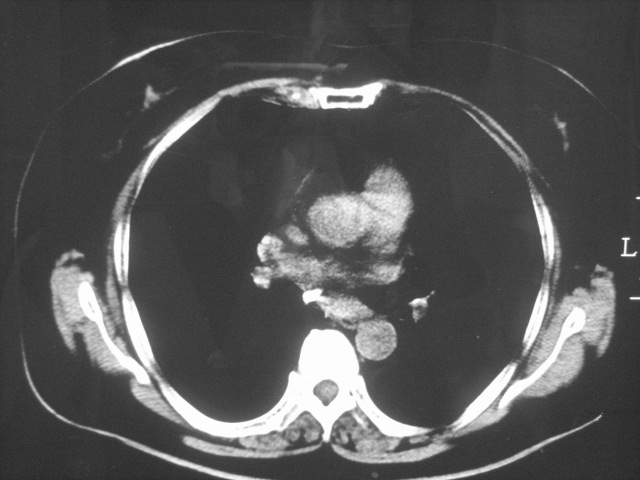

以下是引用清清楚楚在2007-8-28 7:13:00的发言:[br]右肺下叶可见斑片状高密度影,边缘模糊;右肺中叶内侧段及左肺舌段亦可见小斑片状模糊影。[br]考虑双肺感染,建议抗炎治疗后复查。

以下是引用天南地北在2007-8-27 23:49:00的发言:[br]右肺下叶可见斑片状高密度影,边缘模糊;右肺中叶内侧段及左肺舌段亦可见小斑片状模糊影。[br]考虑双肺感染,建议积极抗炎治疗后复查。

以下是引用难听在2007-8-28 13:17:00的发言:[br]右肺下叶背段支气管狭窄,是否可以考虑新生物伴阻塞性肺炎.请大家帮帮忙,这个病人是卫生局长的丈母娘.惹不起啊.